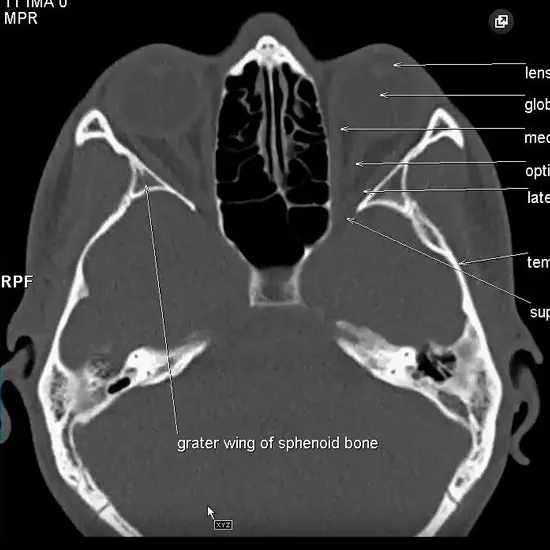

NCCT PNS Axial is a Non-Contrast Computed Tomography scan of para-nasal Sinuses with an Axial view.

It is an imaging technique that would obtain images of the PNS from top to bottom.

Once the image is generated, the black part of the sinuses denotes the presence of air in it.

The scanner would then take several images of the Paranasal Sinus from Axial angle using X-rays. These images would be then processed by the computer to produce the precise 2D images of any internal structures.